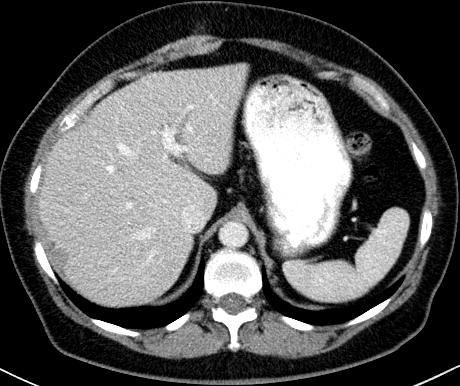

| mild infiltration of the omental fat |

| peritoneal nodular enhancement next to the liver surface, representing metastases with history of ovarian cancer |